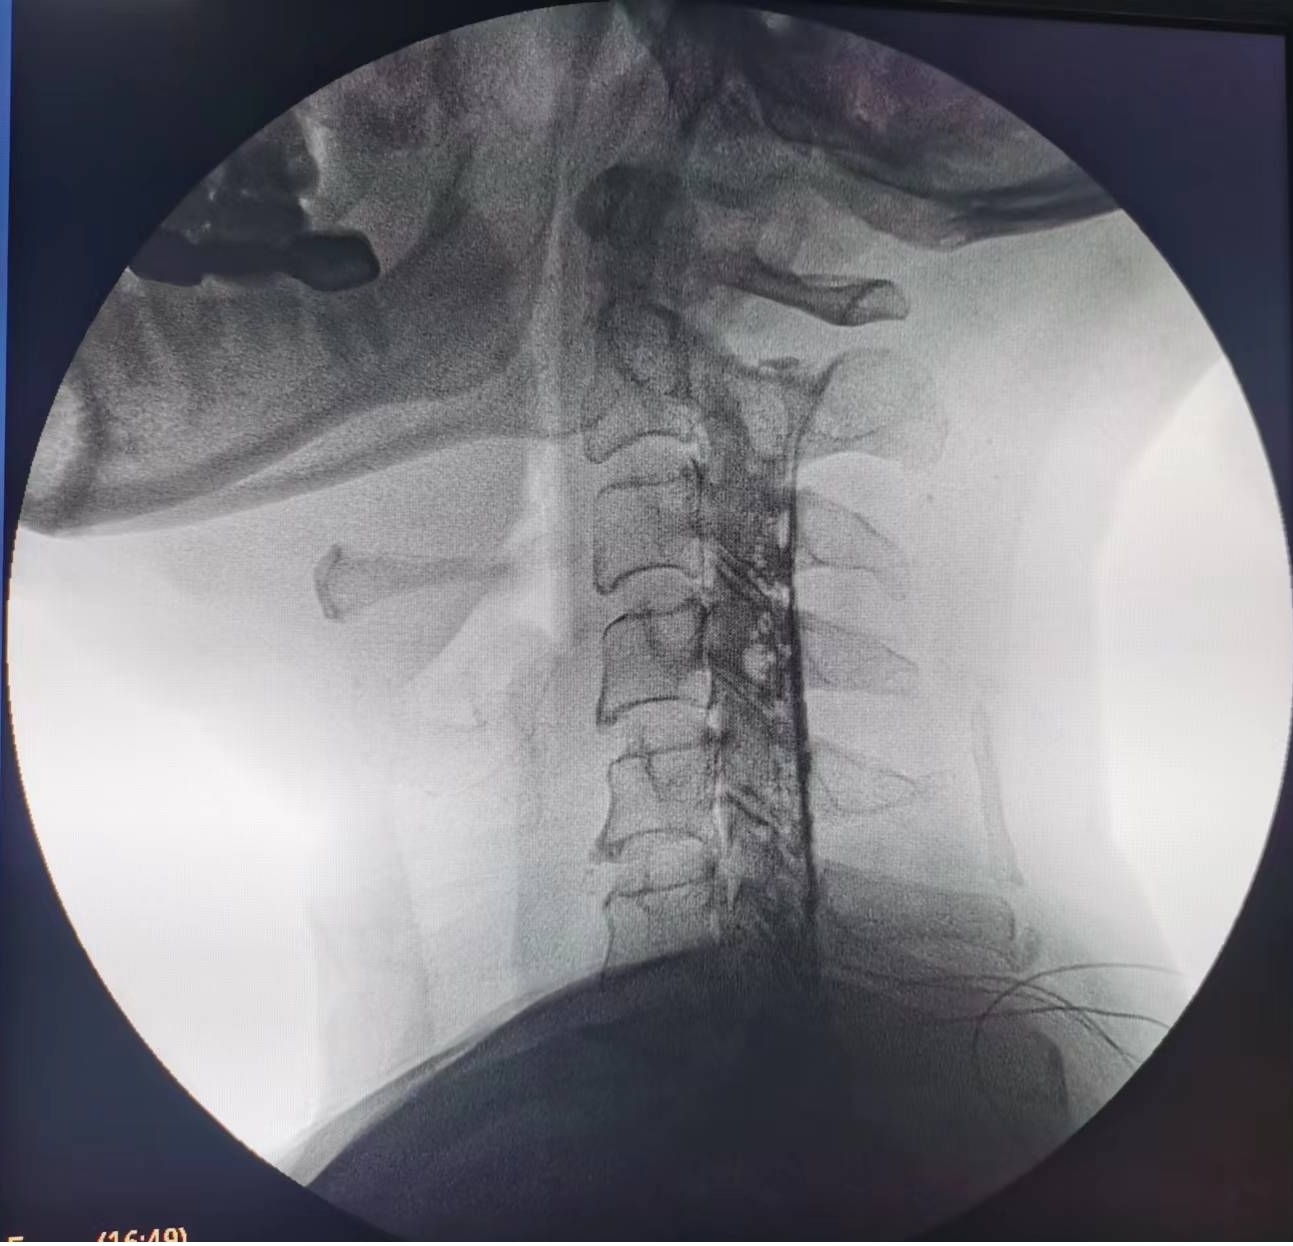

輾轉(zhuǎn)來到瀘州市中醫(yī)醫(yī)院疼痛科治療。由于疼痛嚴(yán)重,外加嚴(yán)重缺乏睡眠,黃大伯入院時(shí)焦慮、精神狀態(tài)很差??粗鼻邢虢獬纯嗟难凵?,疼痛科醫(yī)生團(tuán)隊(duì)抓緊時(shí)間完善診查,發(fā)現(xiàn)黃大伯病情為第6、7節(jié)頸椎間盤突出重,壓迫左側(cè)第7頸神經(jīng)根導(dǎo)致??紤]他年齡較大,團(tuán)隊(duì)決定給他做一種微創(chuàng)手術(shù)——膠原酶化學(xué)溶解術(shù):通過一支細(xì)小的針穿刺到突出的椎間盤,注射膠原酶,將突出的椎間盤溶解掉,以減除神經(jīng)的壓迫。

手術(shù)之后3天,黃大伯疼痛得到很好緩解,露出了許久沒有的笑容,終于可以安心躺著睡覺了,1個(gè)月后基本恢復(fù)了正常生活,6個(gè)月后復(fù)查CT發(fā)現(xiàn)突出的頸椎間盤已經(jīng)基本消失了,黃大伯一家人對(duì)治療效果非常滿意。

手術(shù)之前CT,巨大突出物 術(shù)后6個(gè)月復(fù)查CT:突出物消失